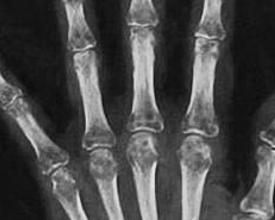

反射性交感神经营养不良综合征(reflex sympathetic dystrophy syndrome,RSDS)是以四肢远端严重疼痛伴自主神经功能紊乱为特征的临床综合征。其命名较多,如灼性神经痛,Sudecks萎缩、创伤后萎缩、肩-手综合征等,目前国际上已逐步统一称为RSDS。